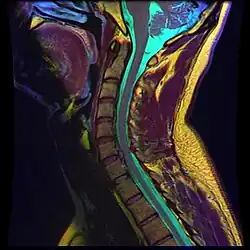

- Magnetic resonance imaging is the gold standard study for confirming a suspected LDH. With a diagnostic accuracy of 97%, it is the most sensitive study to visualize a herniated disc due to its significant ability in soft tissue visualization. MRI also has higher inter-observer reliability than other imaging modalities. It suggests disc herniation when it shows an increased T2-weighted signal at the posterior 10% of the disc. Degenerative disc diseases have shown a correlation with Modic type 1 changes. When evaluating for postoperative lumbar radiculopathies, the recommendation is that the MRI is performed with contrast unless otherwise contraindicated. MRI is more effective than CT in distinguishing inflammatory, malignant, or inflammatory etiologies of LDH. It is indicated relatively early in the course of evaluation (<8 weeks) when the patient presents with relative indications like significant pain, neurological motor deficits, and cauda equina syndrome. Diffusion tensor imaging is a type of MRI sequence used for detecting microstructural changes in the nerve root. It may be beneficial in understanding the changes that occur after herniated lumbar disc compresses a nerve root, and might help in differentiating the patients that need surgical intervention. In patients with a high suspicion of radiculopathy due to lumbar disc herniation, yet the MRI is equivocal or negative, nerve conduction studies are indicated.[44] T2-weighted images allow for clear visualization of protruded disc material in the spinal canal.

MRI scan of cervical disc herniation between C5 and C6 vertebrae

MRI scan of cervical disc herniation between C5 and C6 vertebrae -

MRI scan of cervical disc herniation between C6 and C7 vertebrae

MRI scan of cervical disc herniation between C6 and C7 vertebrae -